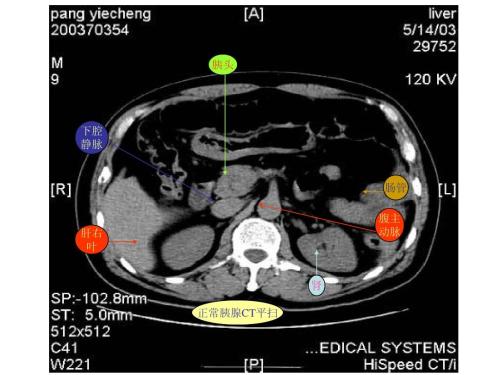

CT是用X射线束对人体某部一定厚度的层面进行扫描,由探测器接收透过该层面的X射线,转变为可见光后,由光电转换变为电信号,再经模拟/数字转换器(analog/digital converter)转为数字,输入计算机处理。图像形成的处理有如对选定层面分成若干个体积相同的长方体,称之为体素(voxel)。

扫描所得信息经计算而获得每个体素的X射线衰减系数或吸收系数,再排列成矩阵,即数字矩阵(digital matrix),数字矩阵可存贮于磁盘或光盘中。经数字/模拟转换器(digital/analog converter)把数字矩阵中的每个数字转为由黑到白不等灰度的小方块,即像素(pixel),并按矩阵排列,即构成CT图像。所以,CT图像是重建图像。每个体素的X射线吸收系数可以通过不同的数学方法算出。

CT的工作程序是这样的:它根据人体不同组织对X线的吸收与透过率的不同,应用灵敏度极高的仪器对人体进行测量,然后将测量所获取的数据输入电子计算机,电子计算机对数据进行处理后,就可摄下人体被检查部位的断面或立体的图像,发现体内任何部位的细小病变。